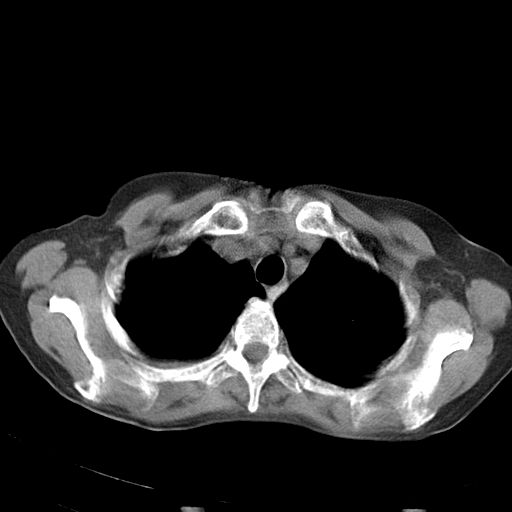

以下是引用dyqct在2006-12-7 21:08:00的发言:[br]考虑:1、肝内外胆管多发性结石伴肝左叶外侧段肝萎缩;[br] 2、右膈下多发脓肿;[br] 3、右侧少量胸腔积液、斜裂积液;[br] 4、左肾囊肿。

以下是引用jiazh在2006-12-7 20:37:00的发言:[br]肝脏周围半狐形低密度影,肝脏表面受压推移,考虑膈下脓肿可能性大;2、右侧胸腔积液

以下是引用拾荒者在2006-12-7 21:44:00的发言:[br]肝内外胆管多发结石,右膈下多发脓肿,右胸膜腔及叶间裂积液,左肾囊肿。[br] [br]